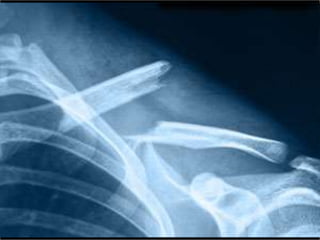

Fracture Clavicule

• Très fréquent

– Chute de vélo

– Chute dans l’escalier

• Position antalgique caractéristique en

fonction de l’âge

Particularités

Nouveauté 2018

• Ibuprofène aussi bon que morphine sans

les effets secondaires!

Conduite

1. Immobilisation